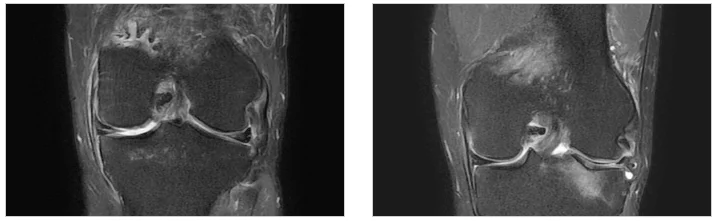

A. 환자 안전은 타협할 수 없는 가치이기 때문입니다. 특히 무릎이나 척추 수술 후에는 환자의 기저 질환이나 신체 반응을 실시간으로 살피는 것이 중요한데, 인력의 눈에만 의존하기보다 데이터라는 객관적인 지표를 활용해 ‘빈틈없는 안전망’을 만들고 싶었습니다.

이러한 시스템은 특히 동탄정형외과 진료를 통해 큰 수술을 받은 환자들에게 유용합니다. 수술 후 마취 회복 과정이나 약물 반응에 따라 나타날 수 있는 미세한 이상 징후를 환자 본인이 자각하기 전에 의료진이 먼저 파악할 수 있기 때문입니다. 체계적인 동탄정형외과입원 관리는 수술 결과만큼이나 환자의 만족도에 큰 영향을 미칩니다. 예를 들어, 수술 후 폐색전증이나 심근경색의 전조 증상은 매우 미세하게 시작되는데, 스마트 시스템은 이를 데이터의 미세한 흔들림으로 잡아냅니다.

특히 무릎 인공관절 수술이나 척추 수술 환자의 경우, 초기 재활 과정에서 발생하는 통증에 대한 두려움이 큽니다. 본원에서는 동탄 허리 신경치료 노하우를 접목하여 환자가 견딜 수 있는 범위 내에서 적합한 통증 조절을 시행하며 재활을 돕습니다. 스마트병동 센서는 재활 운동 중 환자의 심박수 변화를 체크하여 운동 강도가 신체에 무리를 주지 않는지도 모니터링합니다. 무릎 수술 환자의 경우 CPM 장비를 활용해 각도를 0도에서 120도까지 단계적으로 높여가는 정밀한 재활을 시행합니다.